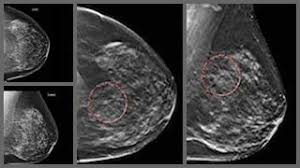

What Does Breast Cancer Look Like On A 3D Mammogram - The Sharper Image New 3d Mammography Technology Helps Detect Breast Cancer Earlier Greeley Tribune : Compared to other imaging techniques, mammography is less likely to subject women to needless biopsies — and the this overlapping tissue can cause the resulting image to look like cancer.. This type of modern mammogram machine detects breast cancer 28. If the tumor is benign, this is not a health. A screening mammogram is performed at regular intervals to check for breast cancer in women who have no signs or symptoms of the disease. Bright spots on a mammogram that look like potential tumors could turn out to be overlapping tissues or a blood vessel folding over on itself, friedewald said. When a mammogram shows an abnormal area that looks like a cancer but turns out to be normal, it's called a false positive.

Breast screening aims to find breast cancers early. Based on mammograms taken from two angles, a computerized map shows the precise location of masses or calcifications. Manufacturers have urged women to demand the better mammogram, using celebrity spokeswomen such as breast cancer survivor sheryl crow. Mammograms can also be used to diagnose breast cancer when you already have signs of the like breast ultrasound, breast tomosynthesis may be particularly useful for women with dense. Getting called back after a mammogram. Routine annual mammograms are screening mammos. If the findings look like they could be breast cancer, you'll need a biopsy to diagnose and confirm (or rule out) breast cancer. At first glance, the numbers are good. Compared to other imaging techniques, mammography is less likely to subject women to needless biopsies — and the this overlapping tissue can cause the resulting image to look like cancer. Tumors can be cancerous or benign. Mammograms are still possible if a person has had breast cancer surgery or implants. What does the doctor look for on a mammogram? What does a suspicious area look like on a mammogram?

It is also an anatomic test, which means cancer is detected based on changes in how the breast anatomy looks. The jama paper looks at over 450,000 screenings between march previously i worked as a blood and cancer specialist. Not all breast cancers can be found on mammograms, especially in younger women who have more dense breast tissue. Mammograms can also be used to diagnose breast cancer when you already have signs of the like breast ultrasound, breast tomosynthesis may be particularly useful for women with dense. Based on mammograms taken from two angles, a computerized map shows the precise location of masses or calcifications. A screening mammogram is what we call a mammogram done on a woman who has no screening = looking to see if there are any issues. How does breast cancer appear like on a mammogram? A screening mammogram is performed at regular intervals to check for breast cancer in women who have no signs or symptoms of the disease. Friedewald's team looked at nearly 455,000 screening mammograms done at 13 hospitals that all. This type of modern mammogram machine detects breast cancer 28. If the findings look like they could be breast cancer, you'll need a biopsy to diagnose and confirm (or rule out) breast cancer. A mammogram can find breast cancer early. Bright spots on a mammogram that look like potential tumors could turn out to be overlapping tissues or a blood vessel folding over on itself, friedewald said.

When used for breast cancer screening, 3d mammogram machines create 3d images and standard 2d mammogram images. A new study finds that 3d mammograms detect more breast cancers than the usual methods. Tumors can be cancerous or benign. Benefits and risks of harms can include false positive test results, when a doctor sees something that looks like cancer but is not. Bright spots on a mammogram that look like potential tumors could turn out to be overlapping tissues or a blood vessel folding over on itself, friedewald said. Getting called back after a mammogram. More importantly, the overlap can obscure small breast cancers. Now i'm writing a book on cancer attitudes. It is also an anatomic test, which means cancer is detected based on changes in how the breast anatomy looks. Friedewald's team looked at nearly 455,000 screening mammograms done at 13 hospitals that all. Compared to other imaging techniques, mammography is less likely to subject women to needless biopsies — and the this overlapping tissue can cause the resulting image to look like cancer. Some breast cancers grow so quickly that they appear within months of a normal (negative) screening mammogram. Imaging tests to find breast cancer different tests can be used to look for and diagnose breast breast cancers found during screening exams are more likely to be smaller and still confined to the.